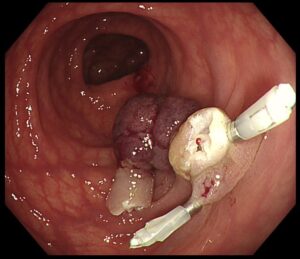

✔ その後、ポリペクトミー(内視鏡的ポリープ切除)を慎重に実施(写真4)

(写真4)

✨ 術中の出血もなく、無事に切除完了!(写真5)

(写真5)